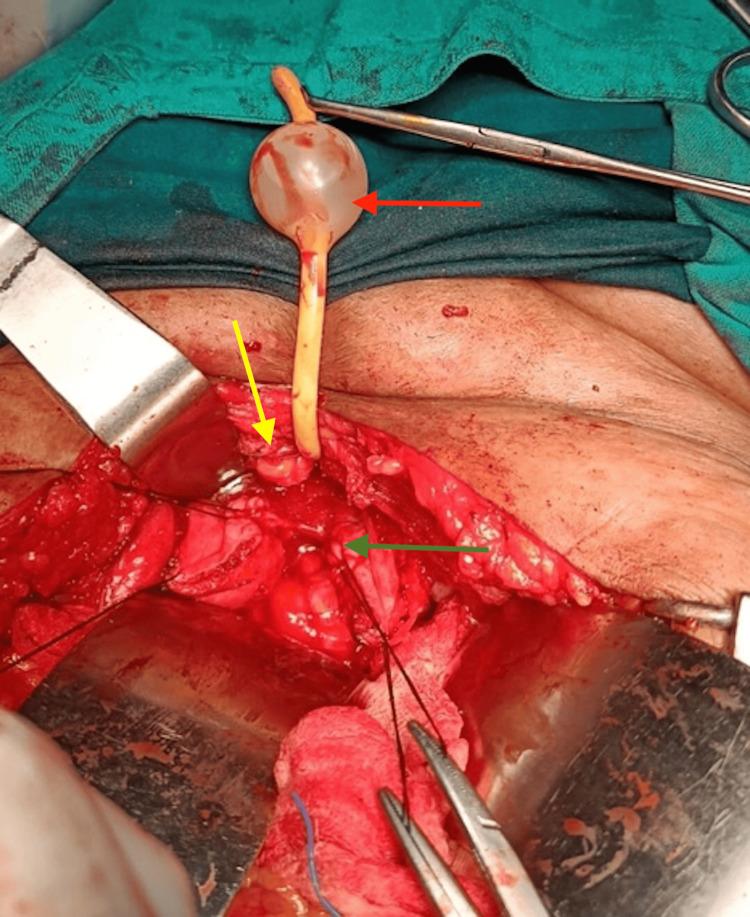

In many developing nations, vesicovaginal fistulas (VVF) continue to be a serious cause of concern. It leads to significant morbidity in urology for women. Patients of VVF experience social rejection as a result of constant dribbling, stink, and wetness, which degrades their quality of life. Hence, this report presents the case of a 45-year-old woman who approached the Outpatient Department of Obstetrics and Gynaecology with complaints of leakage of urine and urinary incontinence for three months with a surgical history of total abdominal hysterectomy. On per-speculum examination, leakage of urine was observed, and on per-vaginal speculum, a rent of 1×2 cm was palpable on the anterior wall of the vagina. For diagnostic assessment, cystoscopy and computed tomography urography confirmed the diagnosis of post-hysterectomy VVF. The surgical intervention involved cystotomy for the supratrigonal fistula, which was 1.5×1.5 cm in size, and the repair was performed by O'Connor's procedure. In conclusion, appropriate preoperative diagnosis, investigations, and principles of surgical intervention lead to improved surgical outcomes.

在许多发展中国家,膀胱阴道瘘(VVF)仍然是一个令人严重关切的问题。它导致女性泌尿外科出现显著的发病率。膀胱阴道瘘患者因持续滴尿、异味和潮湿而遭受社会排斥,这降低了她们的生活质量。因此,本报告介绍了一名45岁女性的病例,该女性因尿液渗漏和尿失禁三个月前来妇产科门诊就诊,有全腹子宫切除术的手术史。经阴道窥器检查时,观察到尿液渗漏,经阴道指诊时,在阴道前壁可触及一个1×2厘米的裂口。为进行诊断评估,膀胱镜检查和计算机断层扫描尿路造影确诊为子宫切除术后膀胱阴道瘘。手术干预包括对大小为1.5×1.5厘米的膀胱三角上瘘进行膀胱切开术,并采用奥康纳手术进行修复。总之,适当的术前诊断、检查和手术干预原则可改善手术效果。